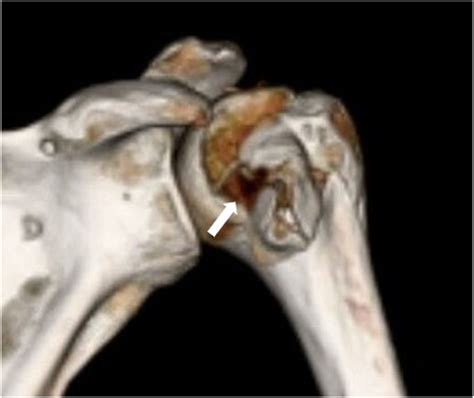

Hill Sachs disease is named after the doctors who first described it, Dr. Harold Arthur Hill and Dr. Maurice Sachs. It is a common complication of shoulder dislocations, particularly anterior dislocations. The condition involves a defect or indentation on the posterolateral aspect of the humeral head, which can range from a small depression to a large, irregular deformity.

When the shoulder dislocates anteriorly, the humeral head is forced out of the glenoid fossa and impacts the anterior glenoid rim. This impact can cause a compression fracture of the humeral head, leading to the characteristic Hill Sachs lesion. The size and location of the lesion can vary, depending on the severity of the dislocation and the individual's anatomy.

• Imaging studies: Imaging studies, such as X-rays, CT scans, or MRI scans, can help visualize the Hill Sachs lesion and assess its size and location. MRI scans are particularly useful for evaluating the soft tissues around the shoulder joint.

• hill sachs defect ct